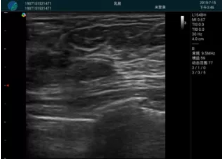

腺體內(nèi)部清晰顯示一低回聲塊影,形態(tài)不規(guī)則,邊界模糊,邊緣呈毛刺狀,內(nèi)部見(jiàn)砂礫樣鈣化

M20引導(dǎo)下穿刺活檢術(shù)

M20引導(dǎo)下平面內(nèi)穿刺取出的腫塊組織